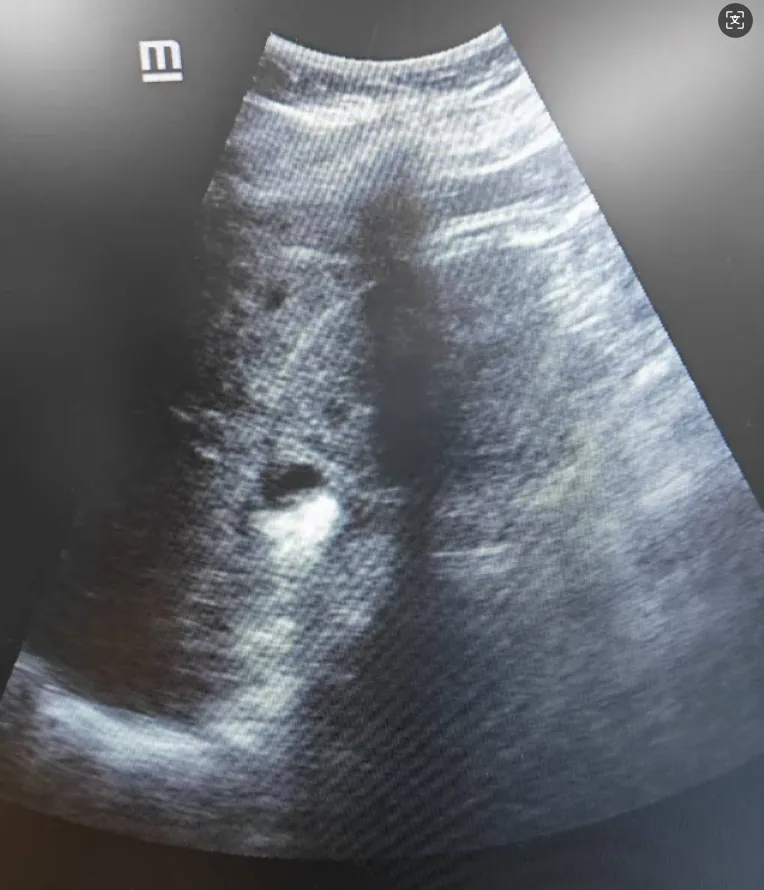

▲憩室内结石

面对这一特殊情况,我院专家团队迅速调整思路,结合术前CT与术中实时超声定位,判断患者可能存在较为特殊的“肾盏憩室结石”。专家团队果断寻及闭合的盏颈口,借助钬激光技术切开后,结石终于显露。主刀医师随后将结石击碎并悉数取出,同时解除了盏颈梗阻,成功完成了手术。